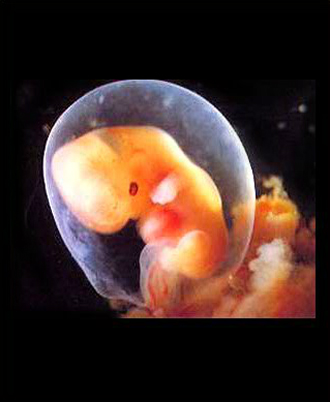

- 10주 이전

- 질 초음파 (1회/2주)